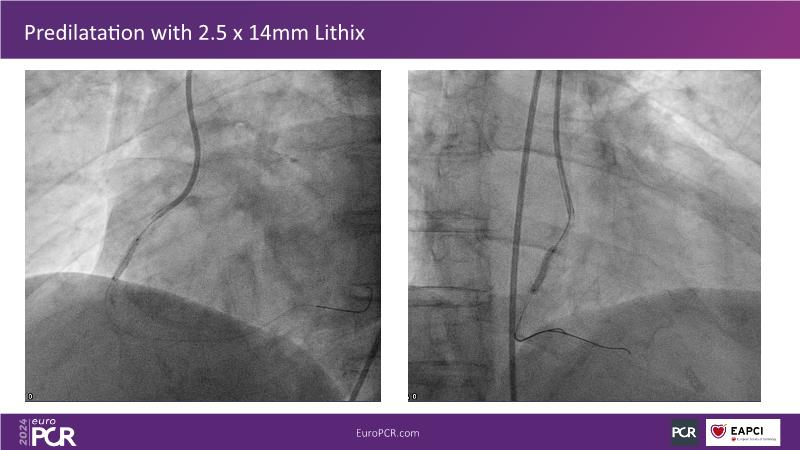

Follow this session to learn about the novel HC-IVL system, its application for moderate to severe calcified lesions, and procedural tips. The LithiX Hertz Contact IVL addresses unmet needs in coronary artery calcification by offering a simplified workflow with fewer devices and effective treatment for difficult lesions. Its novel design ensures safety and efficacy, with the PINNACLE I study's primary outcomes expected to confirm its effectiveness.